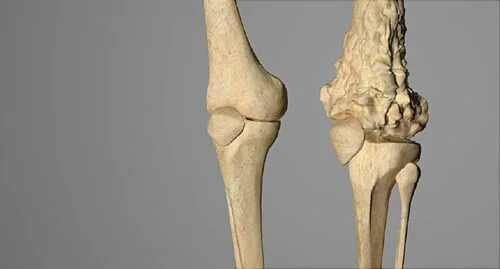

يعد ورم العظام عبارة عن نمو غير طبيعي للخلايا يبدأ في أحد العظام؛ كما يمكن أن ينشأ في أي عظم، ولكنه في الغالب يصيب عظم الفخذ؛ لا يتضمن مصطلح “ورم العظام” الأنواع التي تنشأ في جزء آخر من الجسم ثم تنتشر إلى العظام؛ بل يطلق على الورم الذي ينتقل إلى العظام الاسم الذي بدأ منه؛ على سبيل المثال السرطان الذي يبدأ في الرئتين وينتقل إلى العظام يبقى معروفًا بسرطان الرئة وقد يشير متخصصو الرعاية الصحية إليه بسرطان الرئة الذي انتشر إلى العظام؛ كما أن من النادر حدوث السرطان في العظام؛ هناك أنواع متنوعة من سرطانات العظام، حيث تلاحظ بعض الأنواع بشكل رئيسي عند الأطفال، بينما تسجل أنواع أخرى في الغالب لدى البالغين.

يعتبر ورم العظام نوع نادر من الاورام، حيث يحدث عندما تبدأ خلايا العظام أو أي نوع منها في النمو والتكاثر بشكل غير طبيعي وبطريقة مفرطة وخارج السيطرة؛ حيث تتكون العظام من نوعين من الخلايا، وهما: